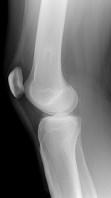

问题 女性,39岁。发现左大腿下段后部有一包块,质较硬,无明显疼痛感觉,请结合所提供的图像,选择最佳选項()

选项 A.软骨肉瘤 B.软骨瘤 C.骨肉瘤 D.骨软骨瘤 E.骨瘤

答案 D